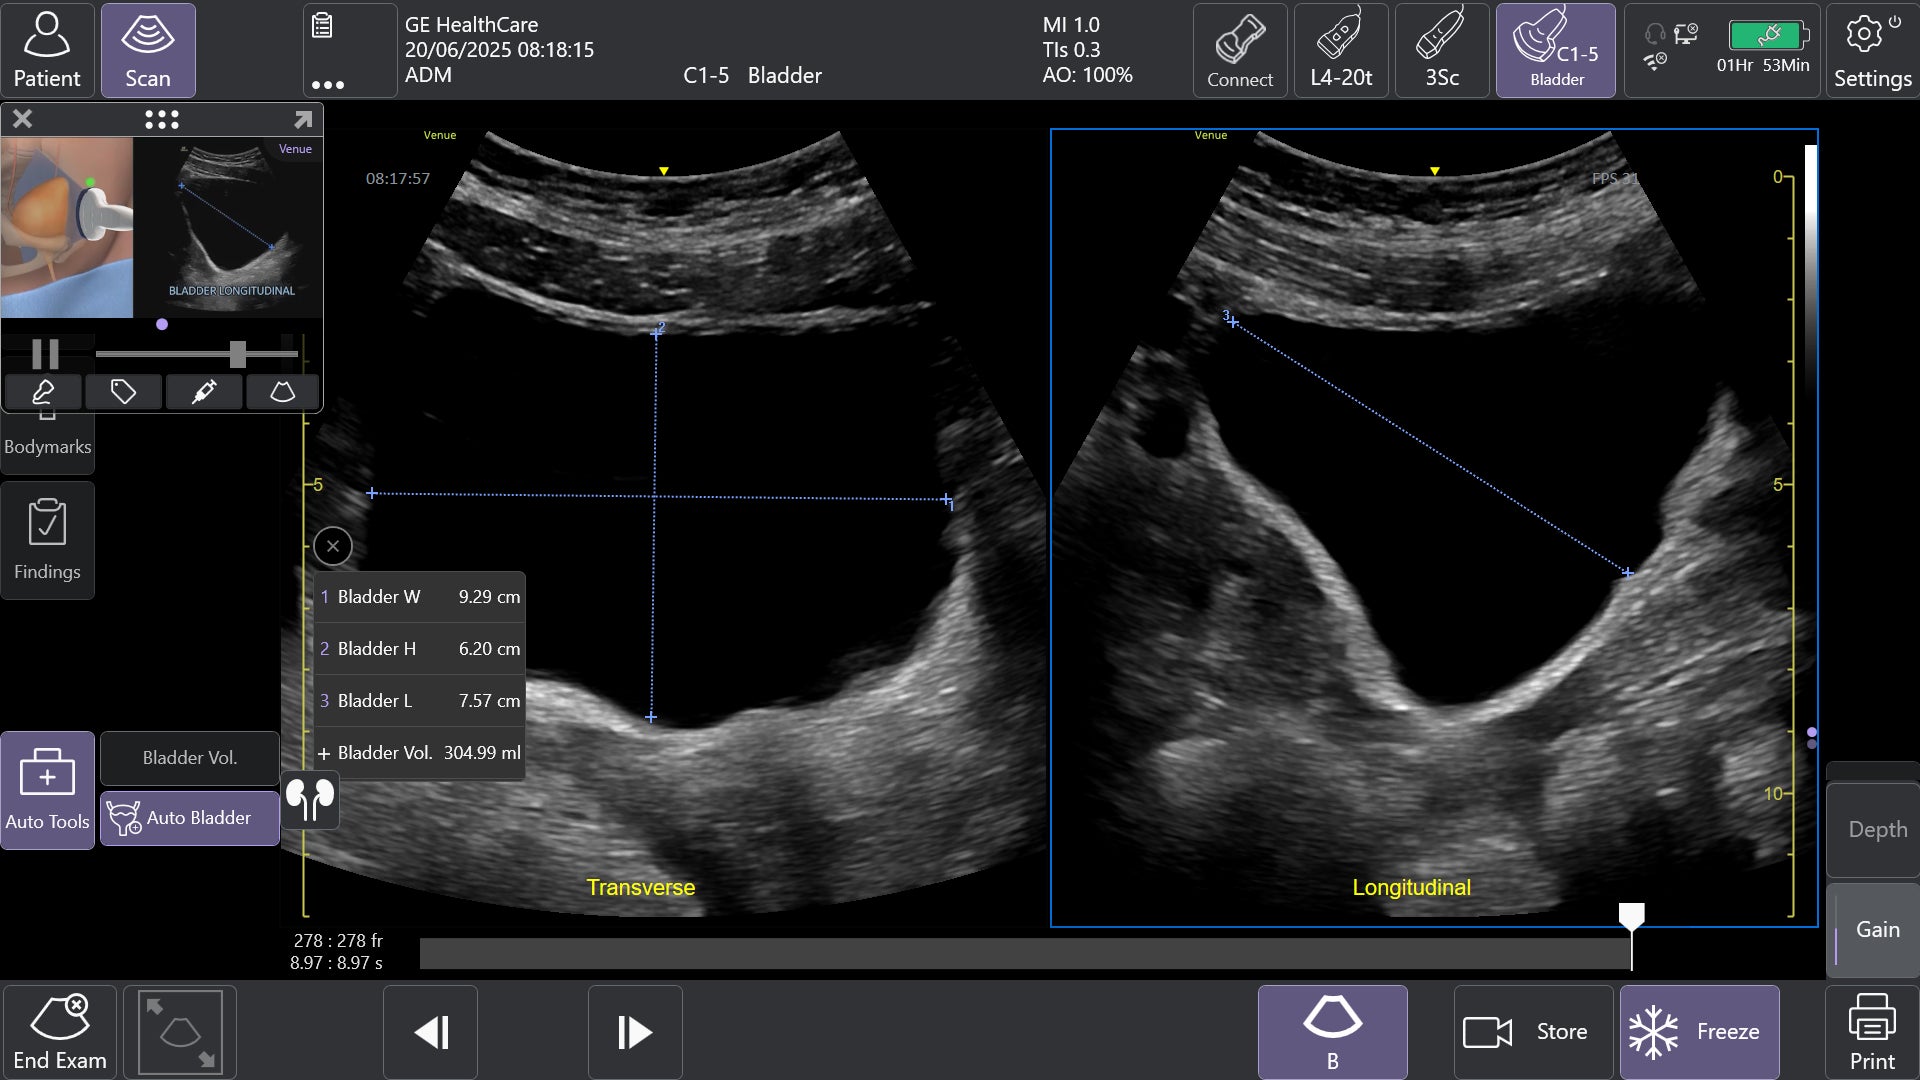

②AIツールAuto Bladder Volume(オートブラッダーボリューム)で膀胱評価を効率化

AIを用いて開発されたAuto Bladder Volumeは、膀胱の容積を半自動で計測するツールです。横断像および縦断像の2方向の画像から、AIが自動的に膀胱形状を認識し容積を算出するため、再現性の高い評価が可能になります。

救急外来や集中治療室、手術後、病棟など様々な場面での活用が想定され、侵襲的な処置を行う事なく迅速かつ効率的な膀胱容積評価が可能となります。